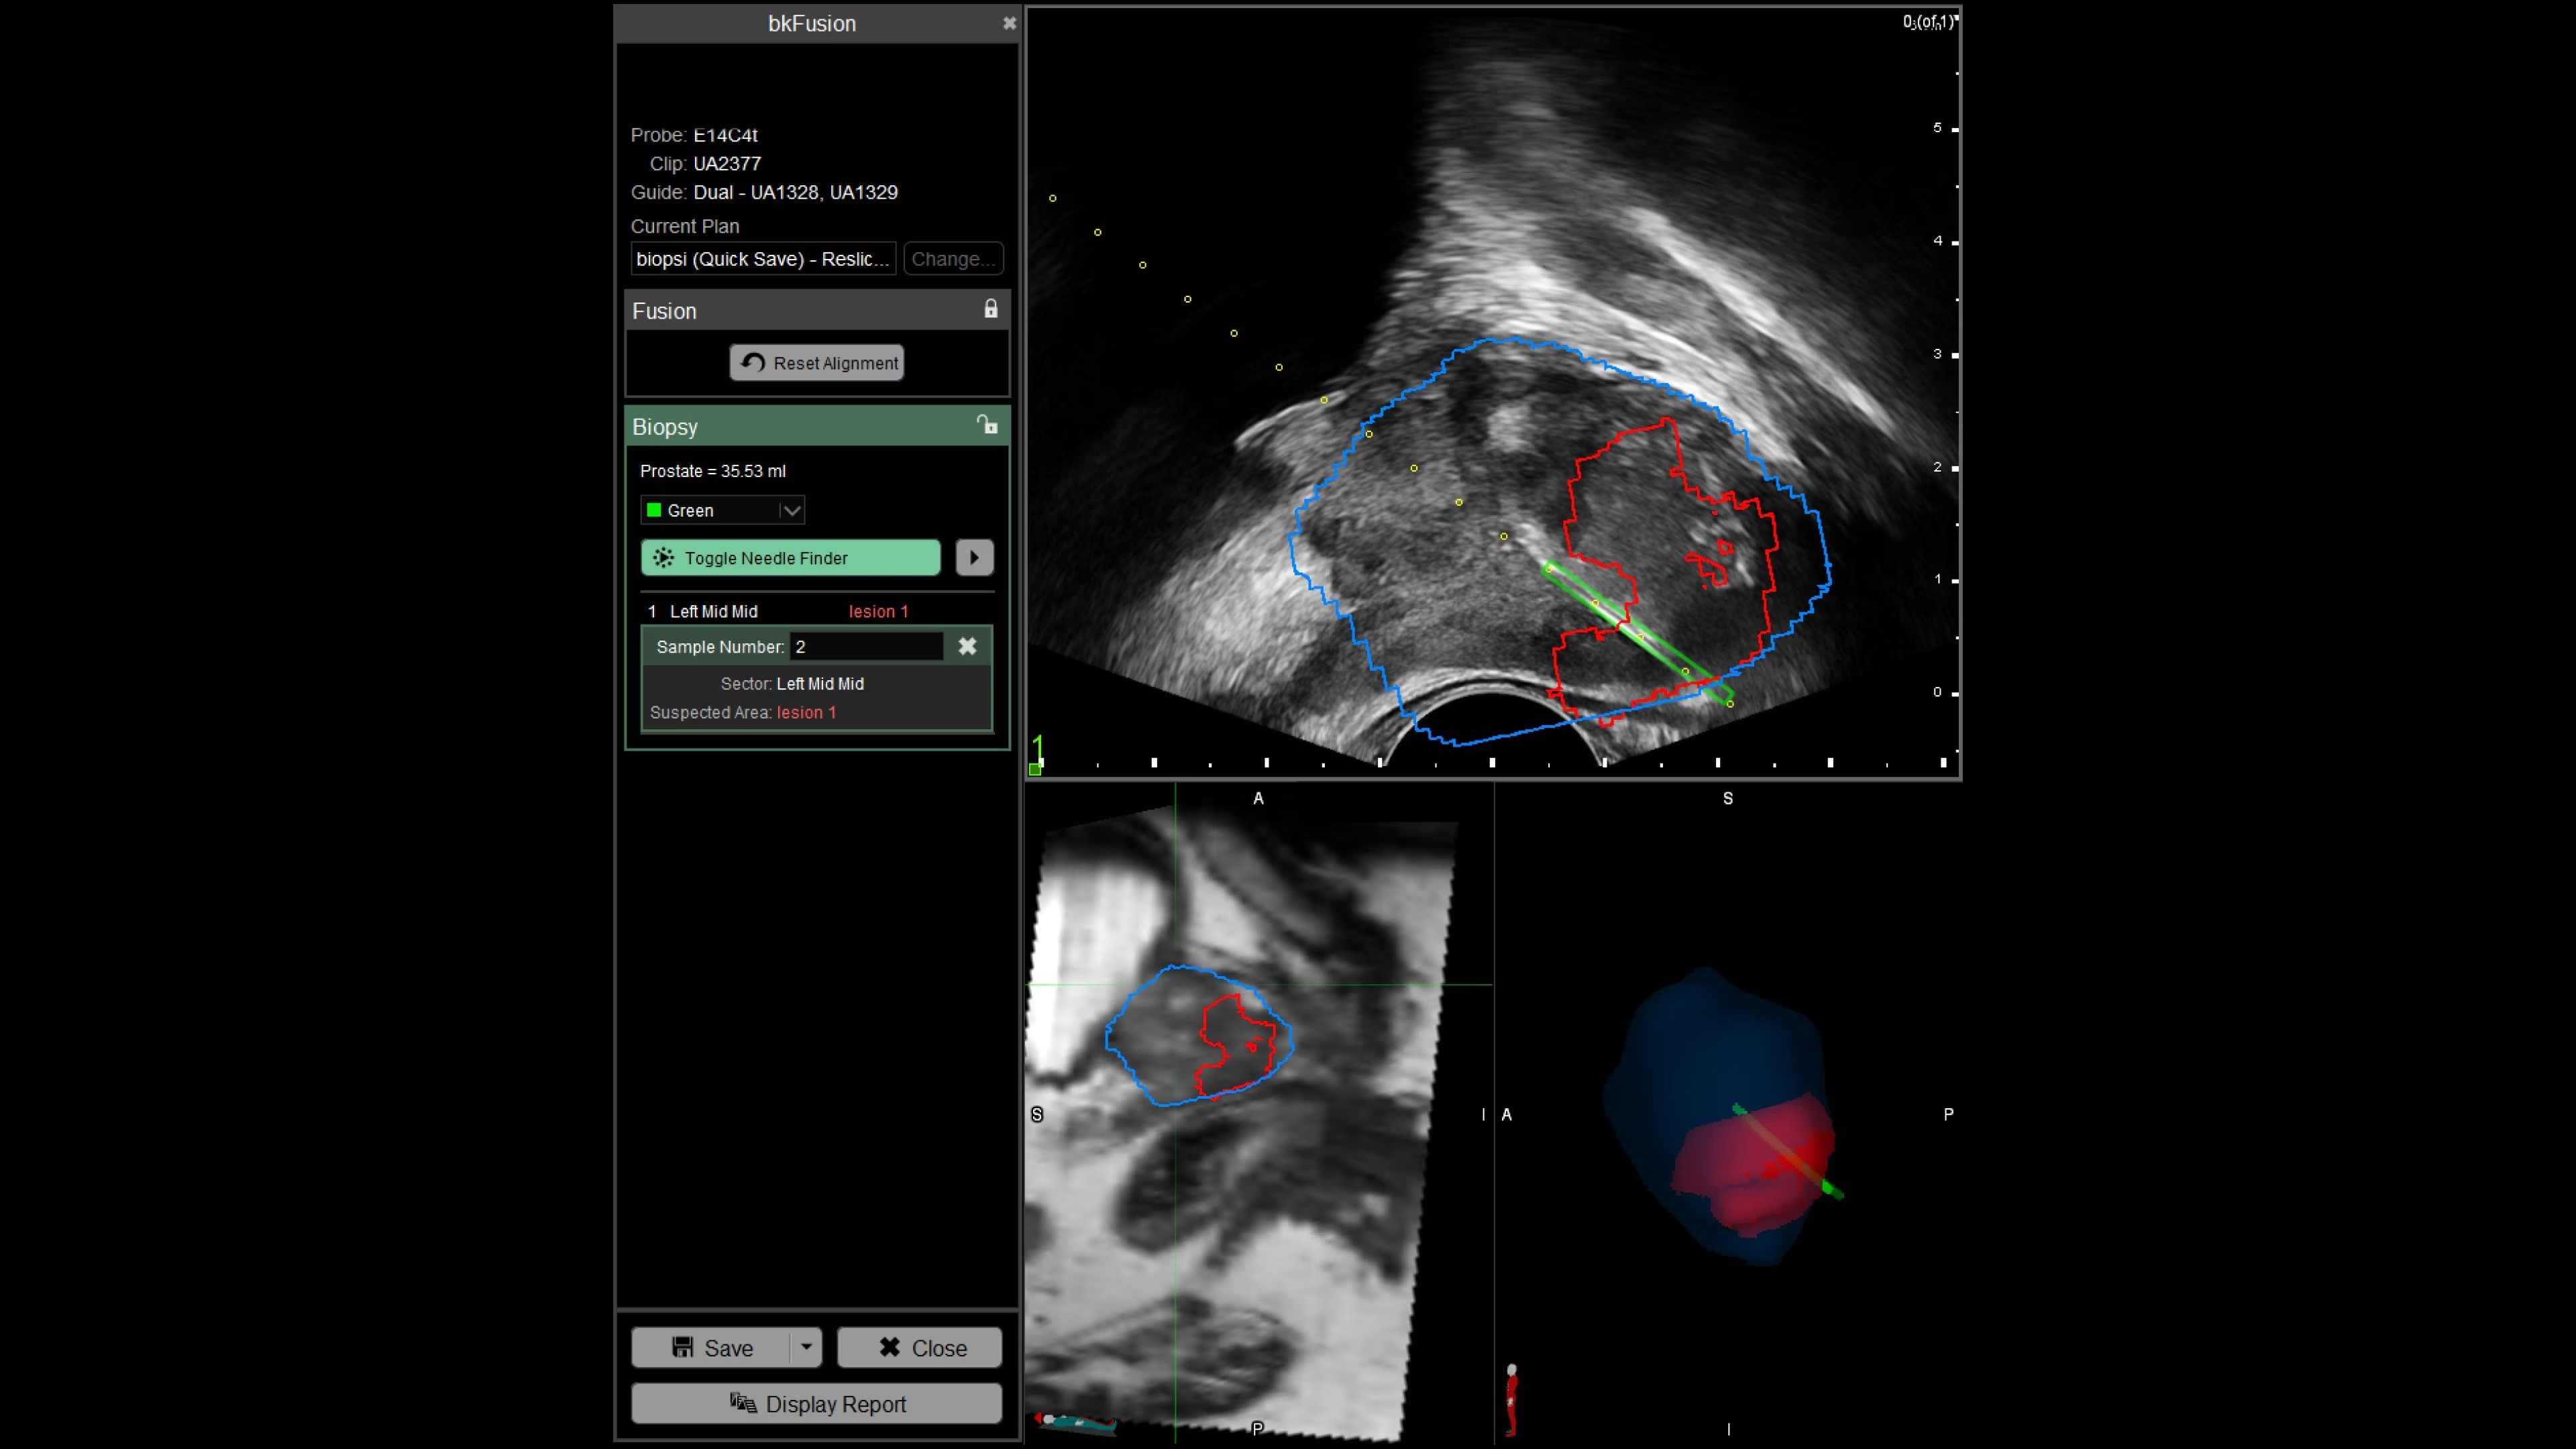

Enhance biopsy accuracy with Predictive Fusion®

Predictive Fusion® is the proprietary registration method allowing you to imediately see any errors in the overly of MRI and ultrasound images before and during the procedure. Utilizing rigid 2D slice registration, it eliminates distortion in merging 3D shapes, ensuring precise MRI-ultrasound fusion. If changes are needed, make simple, one-touch, micro-adjustments to updte the registration without calibration steps or 3D sweeps. Enhance your prostate biopsy accuracy with this advanced technology.

Explore versatile biopsy techniques with bkFusion

bkFusion evolves with your practice, offering transperineal stabilized and freehand, or transrectal endfire and sidefire techniques, supported by sterilizable transducers. The TP approach reduces infection risk and suits office or OR settings, showing high patient tolerability and negligible infection rates. Choose between freehand or stabilized approaches, with flexibility for office or OR settings.